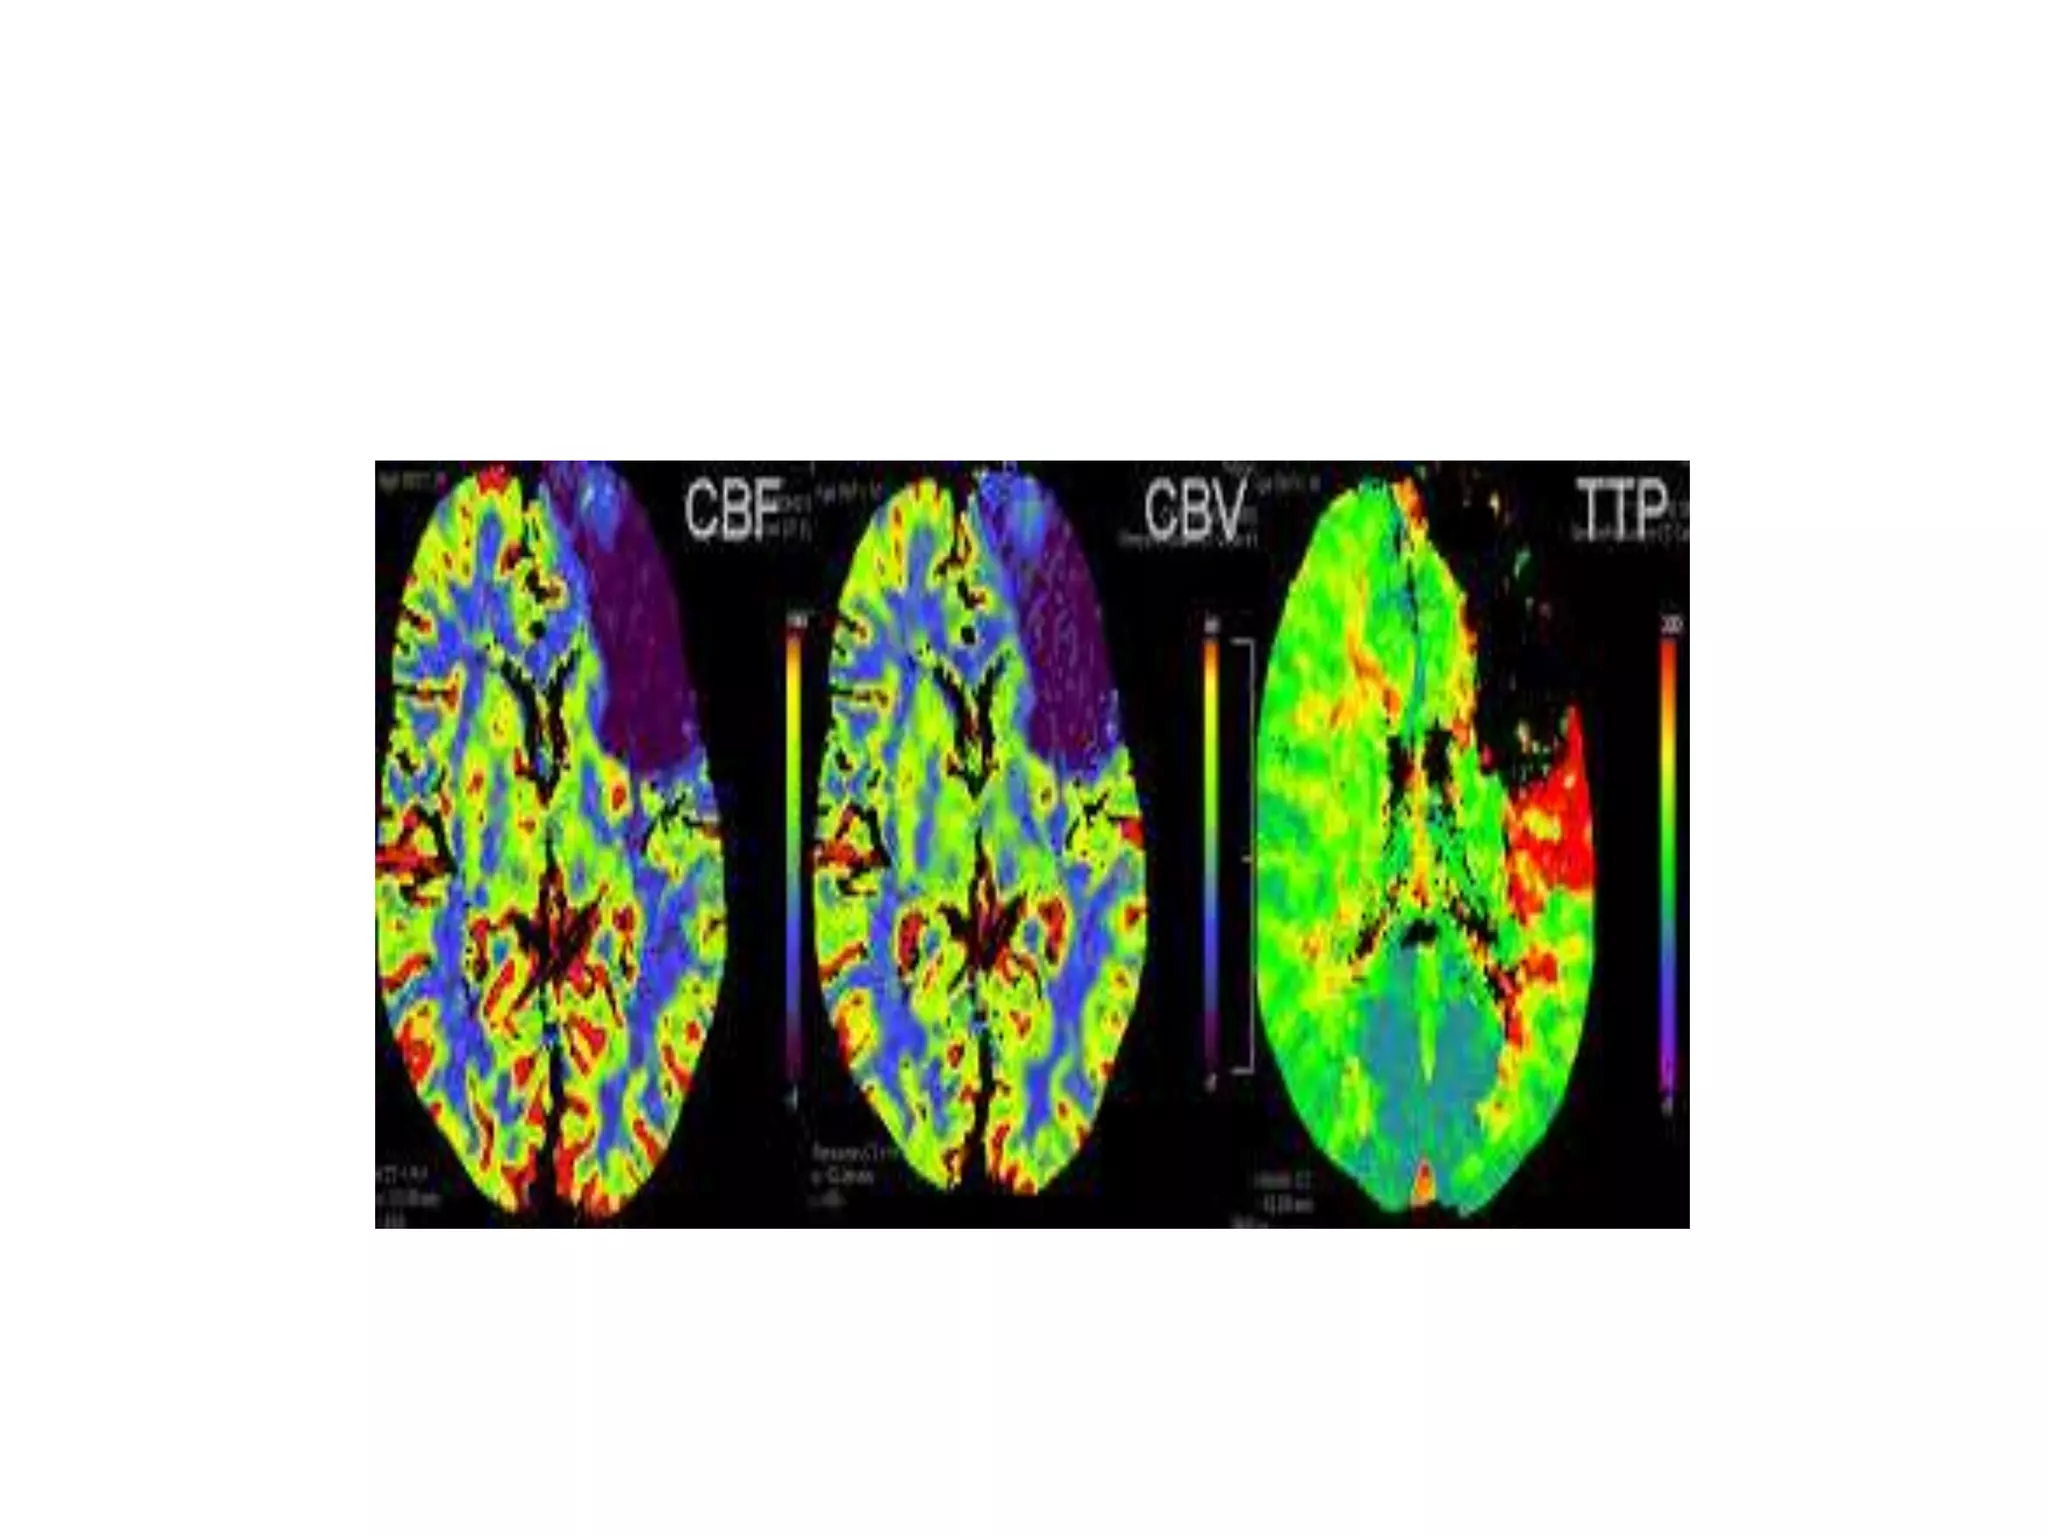

Perfusion Weighted Imaging (PWI)

• Perfusion imaging measures signal reduction

induced in the brain during passage of injected

paramagnetic contrast agents which

induce magnetic susceptibility effects (T2*).

• Yields regional cerebral blood volume (rCBV).

Similarly mean transit time (MTT), total blood

flow (rCBF), time to arrival (TTA) or time to

peak (TPP)

PWI in Stroke

• ischemic penumbra, i.e. ‘functionally

impaired but not irreversibly damaged’ area

around an established infarction is

identified when areas of PWI and DWI

defect are compared

• MRI stroke protocol should include T2 FSE

and FLAIR sections of brain followed by

MRA, DWI, PWI and a GRE sequence for

hemorrhage.

• This comprehensive protocol should take

less than 15 minutes on a modern state of

the art MR scans